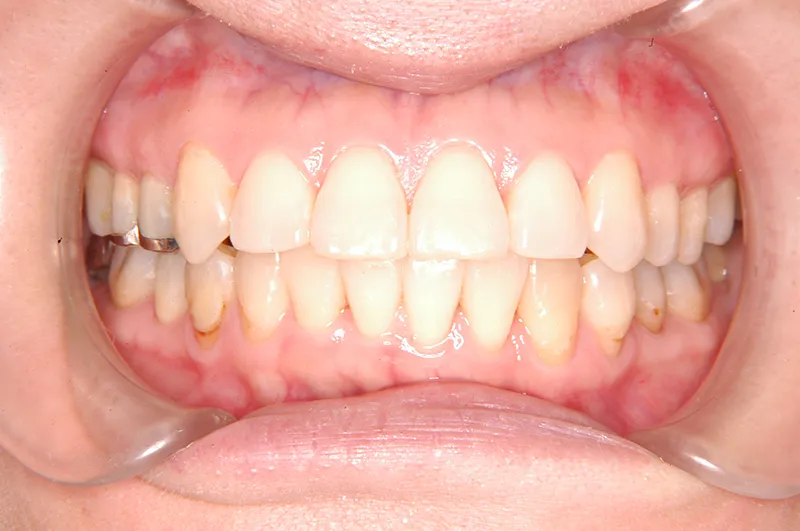

治療終了2年後

噛み合わせが安定する事で、大きくなっていた咬筋が正常な大きさになり、顎のラインもシャープになり大変よろこばれていました。

また今回の症例は、歯科矯正用アンカースクリューを用いた治療の本に掲載されました。